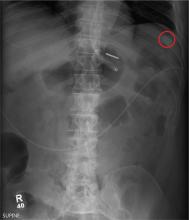

You receive a call from an ICU nurse regarding a patient your service is following—a 60-year-old man who was admitted for altered mental status and is being worked up for a possible brain mass. He has no other significant medical history. The nurse has placed a nasogastric feeding tube to facilitate nutrition and medication administration and has ordered a portable abdominal radiograph to confirm its placement. The completed radiograph is shown. What is your impression?

The radiograph demonstrates a normal gas pattern with a properly placed enteric feeding tube, which appears to be within the stomach. Of note is a sclerotic-appearing lesion on the posterior aspect of the left eighth rib. In a patient with a possible tumor, this lesion ­poses concern for potential metastasis and warrants appropriate work-up.